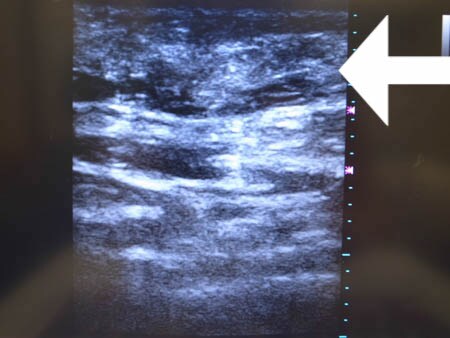

いつものように3Dタッチビュー(超音波)で

皮下脂肪層を評価してみましょう。

上腹部

上の画像の部分の皮下脂肪層をつまんでみましょう。

同様に下腹部 ↓ ↓ ↓

3Dタッチビューでしっかりと

皮下脂肪層をパソコンの画面上に映し出し

皮下脂肪の取り残しがないか?

均一に吸引されているか?

二重、三重のチェックをしていますので

手術が終了した時点ですでに

患者様に対しては確実な効果を

お約束することができます。